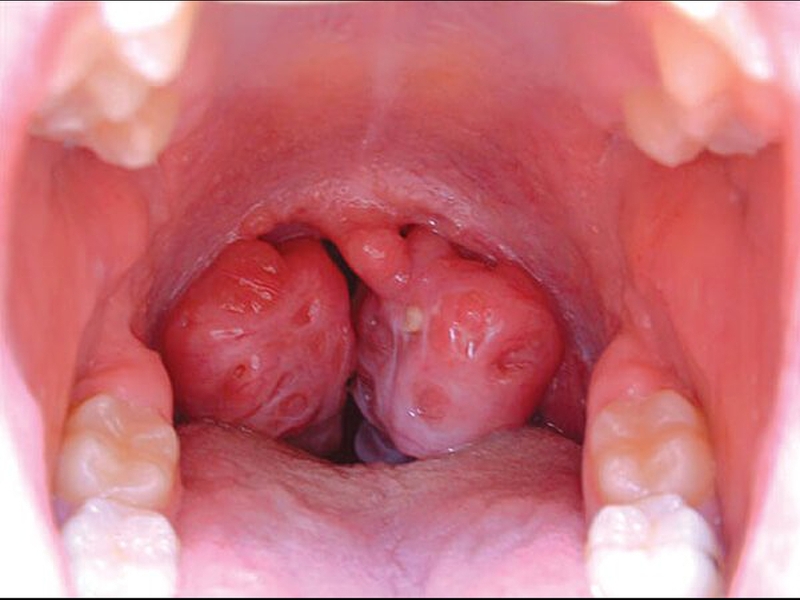

Trước khi tìm hiểu ung thư vòm họng nên ăn gì, bạn cũng nên nắm được ung thư vòm họng là gì? Ung thư vòm họng là bệnh lý ác tính ảnh hưởng nghiêm trọng tới sức khỏe người bệnh. Bệnh thường có những biểu hiện triệu chứng ở vùng mũi họng nên rất dễ nhầm với các bệnh lý của đường hô hấp. Điều này khiến người bệnh chủ quan, thường đi khám bệnh chậm trễ và phát hiện ra bệnh khi bệnh đã ở giai đoạn muộn. Ở Việt Nam, ung thư vòm họng chiếm tỷ lệ tương đối cao, khoảng 3% trong tổng số các bệnh ung thư được chẩn đoán hàng năm. Trong đó có tới 70% bệnh nhân mắc bệnh ung thư vòm họng phát hiện bệnh ở giai đoạn muộn, khiến việc điều trị bệnh trở nên khó khăn và kém hiệu quả.

Trước khi tìm hiểu bị ung thư vòm họng nên ăn gì, việc nắm được những biểu hiện của bệnh ung thư vòm họng để phát hiện và điều trị bệnh sớm là vô cùng cần thiết. Theo các chuyên gia, bệnh nhân ung thư vòm họng thường có các biểu hiện như sau: